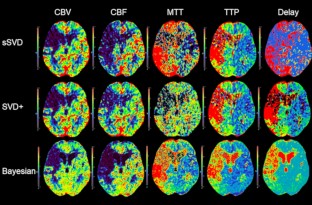

Comparison of a Bayesian estimation algorithm and singular value decomposition algorithms for 80-detector row CT perfusion in patients with acute ischemic stroke

A variety of postprocessing algorithms for CT perfusion are available, with substantial differences in terms of quantitative maps. Although potential advantages of a Bayesian estimation algorithm are suggested, direct comparison with other algorithms in clinical settings remains scarce. We aimed to compare performance of a Bayesian estimation algorithm and singular value decomposition (SVD) algorithms for the assessment of acute ischemic stroke using an 80-detector row CT perfusion.

CT perfusion data of 36 patients with acute ischemic stroke were analyzed using the Vitrea implemented a standard SVD algorithm, a reformulated SVD algorithm and a Bayesian estimation algorithm. Correlations and statistical differences between affected and contralateral sides of quantitative parameters (cerebral blood volume [CBV], cerebral blood flow [CBF], mean transit time [MTT], time to peak [TTP] and delay) were analyzed. Agreement of the CT perfusion-estimated and the follow-up diffusion-weighted imaging-derived infarct volume were evaluated by nonparametric Passing–Bablok regression analysis.

CBF and MTT of the Bayesian estimation algorithm were substantially different and showed a better correlation with the standard SVD algorithm (ρ = 0.78 and 0.80, p < 0.001) than with the reformulated SVD algorithm (ρ = 0.59 and 0.39, p < 0.001). There is no significant difference in MTT only when using the reformulated SVD algorithm (p = 0.217). Regarding the regression lines, the slope and intercept were nearly ideal with the Bayesian estimation algorithm (y = 2.42 x-6.51; ρ = 0.60, p < 0.001) in comparison with the SVD algorithms.

The Bayesian estimation algorithm can lead to a better performance compared with the SVD algorithms in the assessment of acute ischemic stroke because of better delineation of abnormal perfusion areas and accurate estimation of infarct volume.